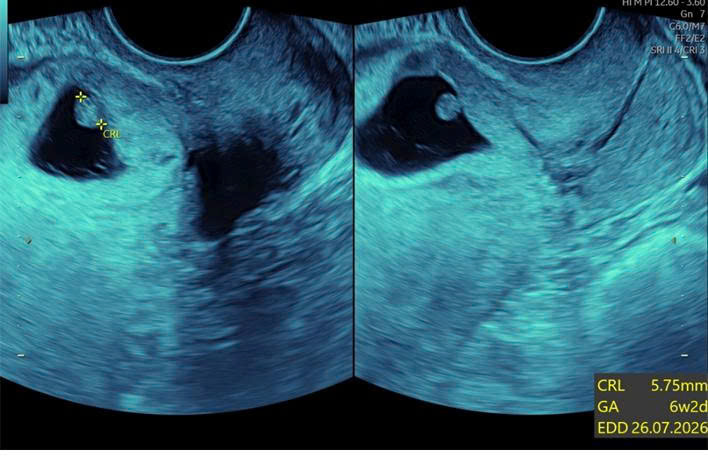

Ấy vậy mà kết quả siêu âm lại khiến chị H. 36 tuổi đã trải qua 2 lần sinh mổ không khỏi bàng hoàng: trong lòng tử cung không thấy thai, nhưng ngay vết sẹo mổ cũ trước đây lại xuất hiện một túi thai có tim thai 6,5 tuần.

Đó là một dạng thai bám vết sẹo mổ cũ – một thể đặc biệt của thai ngoài tử cung. Nghe qua thì nhẹ, nhưng thực tế lại vô cùng nguy hiểm vì thai có thể ăn sâu vào vết sẹo, gây vỡ tử cung hoặc chảy máu ồ ạt khi thai lớn lên, thậm chí đe dọa tính mạng và có nguy cơ không giữ được tử cung.

Hình siêu âm